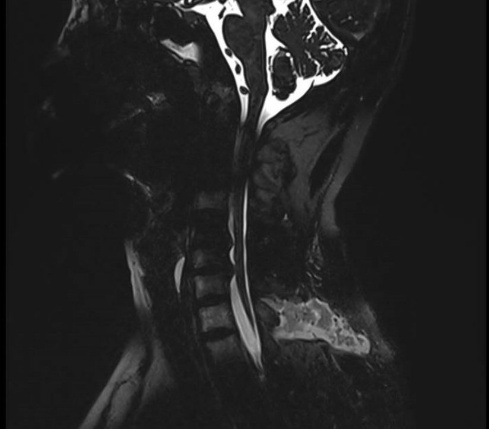

立竿见影——术后三天,头痛完全消失

术前术后影像对比

术后复查